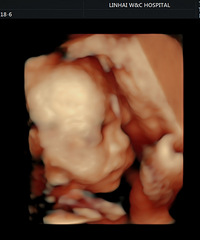

预产期:2022.11.11建卡医院:台州市妇女儿童医院产检医院:台州市妇女儿童医院胎宝宝小名:虎墩生产医院:台州市妇女儿童医院B超照片/孕期相关照片一